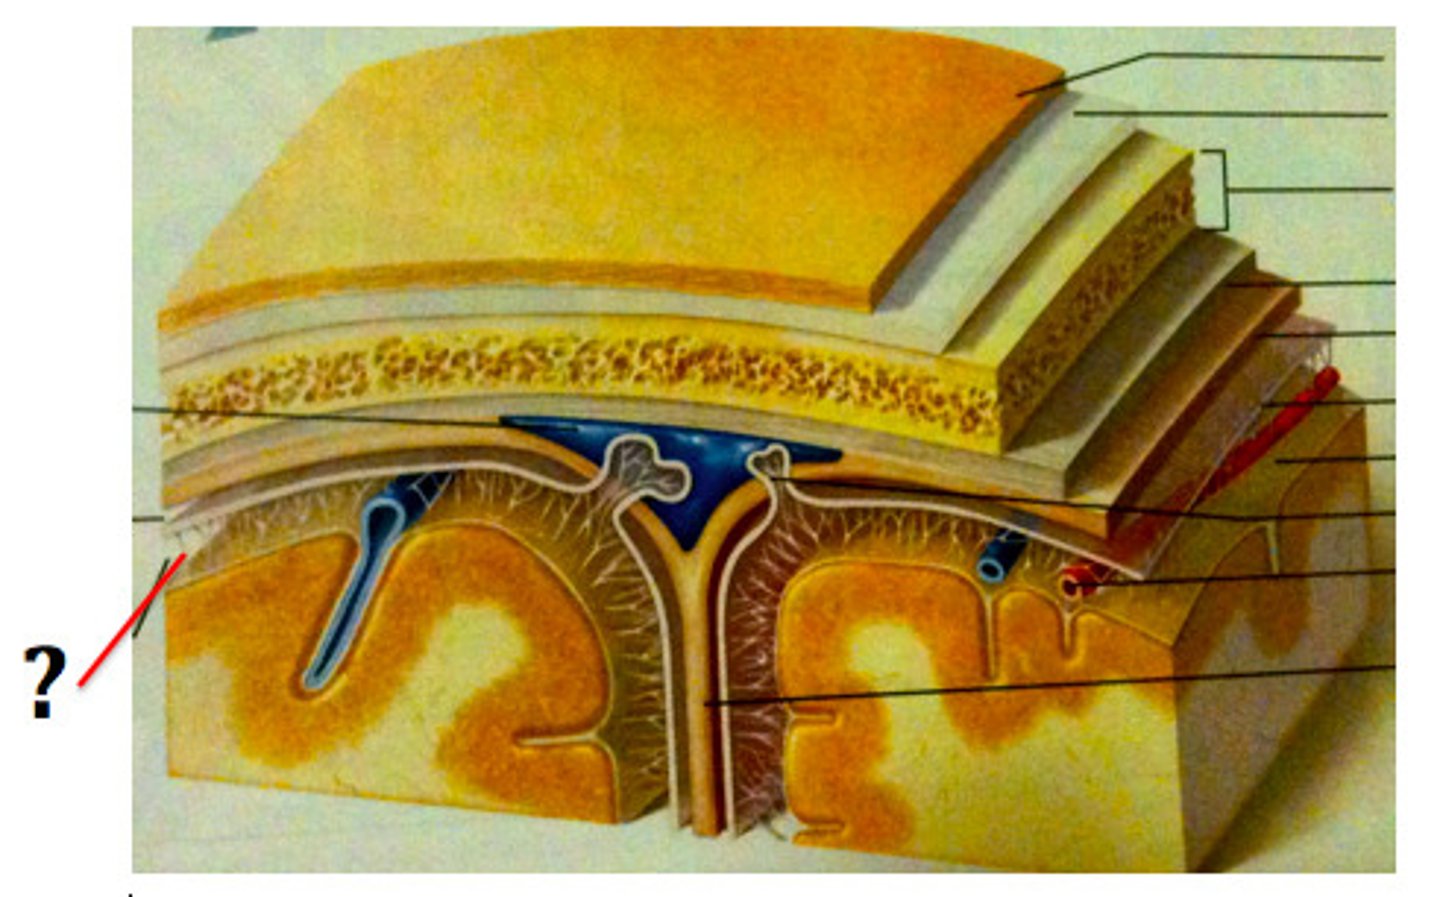

3 layers make up the meninges

dura mater, arachnoid mater, pia mater

dura mater

outer periosteal layer & inner meninges layer

periosteal and meningeal

arachnoid

middle layer of meninges; weblike appearance that attaches it to deepest layer

arachnoid trabeculae

subdural space

space between dura mater and arachnoid mater

subarachnoid space

arachnoid mater

pia mater

the delicate innermost membrane enveloping the brain and spinal cord.

clear, colourless fluid that circulates within the brain and spinal cord, serving several important functions in the CNS

Circulation of CSF

CSF from the lateral ventricles → interventricular foramina → third ventricle → cerebral aqueduct → fourth ventricle → subarachnoid space or central canal.